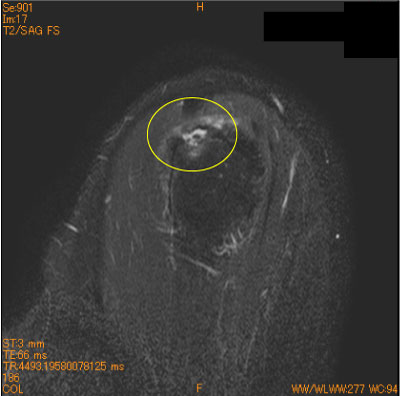

棘上筋腱停止部剥離(滑液包側部分断裂)-肩関節MRI-

60代男性、夜間痛。

棘上筋腱停止部の大結節superior facetからの剥離をみることがある。

腱自体の断裂ではないが、広義の滑液包側部分断裂に分類される。

疼痛肩では、大結節が腱板に被われていることを確認する必要がある。

![]() Obl. Sag T2WI 脂肪抑制 |